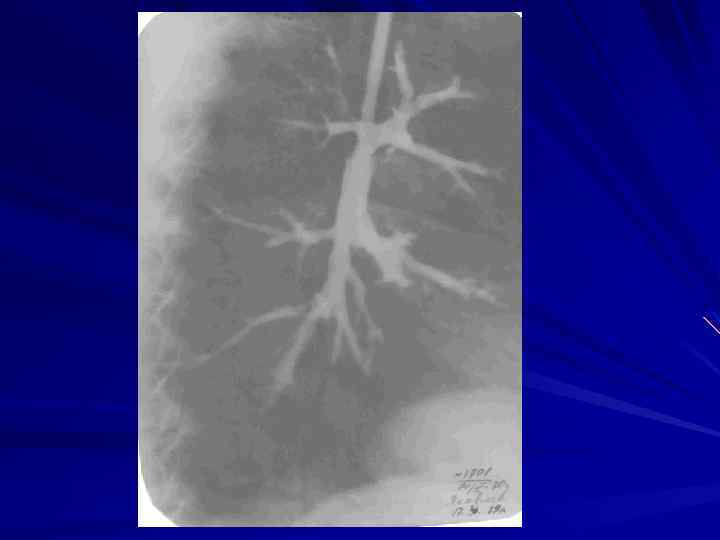

Морфология хронического бронхита: - увеличение в 1, 5 раза толщины стенок бронхов; - гипертрофия бронхиальных слизистых желез и бокаловидных клеток; - участки воспаления, склероза, дистрофических и атрофических изменений всех стенок бронхов (панбронхит); - гнойное пропитывание стенки бронхов с участками изъязвления (возможность кровотечения). - пневмофиброз, эмфизема легких. - развитие бронхоэктазов.

Диагностика хронического бронхита. - Кровь (эритроцитоз, увеличение гематокрита и вязкости крови, при обострении: лейкоцитоз, нейтрофиллез, СОЭ. - Мокрота (нейтрофильный лейкоцитоз, клетки бронхиального эпителия, эритроциты, макрофаги, нарушение реологических свойств). - Рентгенограмма грудной клетки (пневмофиброз, эмфизема легких, низкое стояние диафрагмы и снижение ее экскурсии). - Бронхография (выявление бронхоэктазов). - Бронхоскопия (исследование слизистой бронхов, производство биопсии).